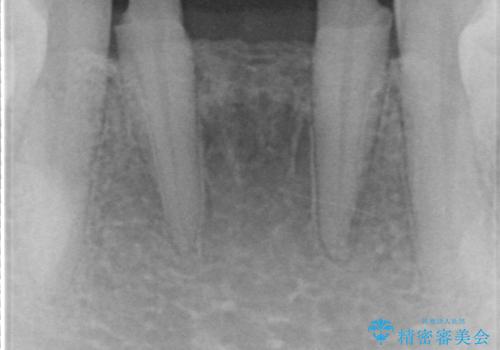

今回は、丈夫な欠けにくいフルジルコニア(ヴェレッツァ)クラウンでブリッジにすることにしました。

- 32万円(下顎2−2:フルジルコニアクラウン(ヴェレッツァクラウン・スタンダード)7万円x4本、仮歯1万円x4本)費用は治療当時の料金となります

装着後、特に問題なく使用されています。